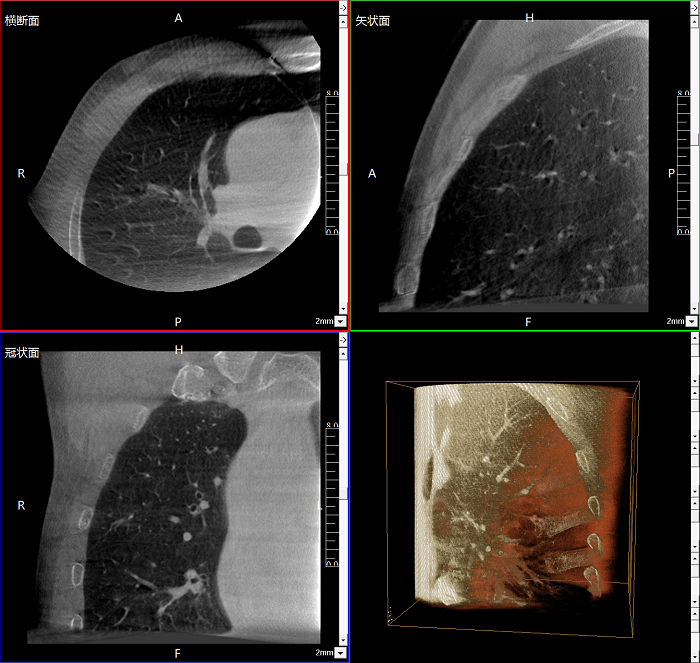

三維成像 全面觀察

任意視角、任意切面觀察

術中實時生成橫斷面、矢狀面、冠狀面及三維影像,可在任意切面、任意角度評估植入物和解剖結構的相對位置。